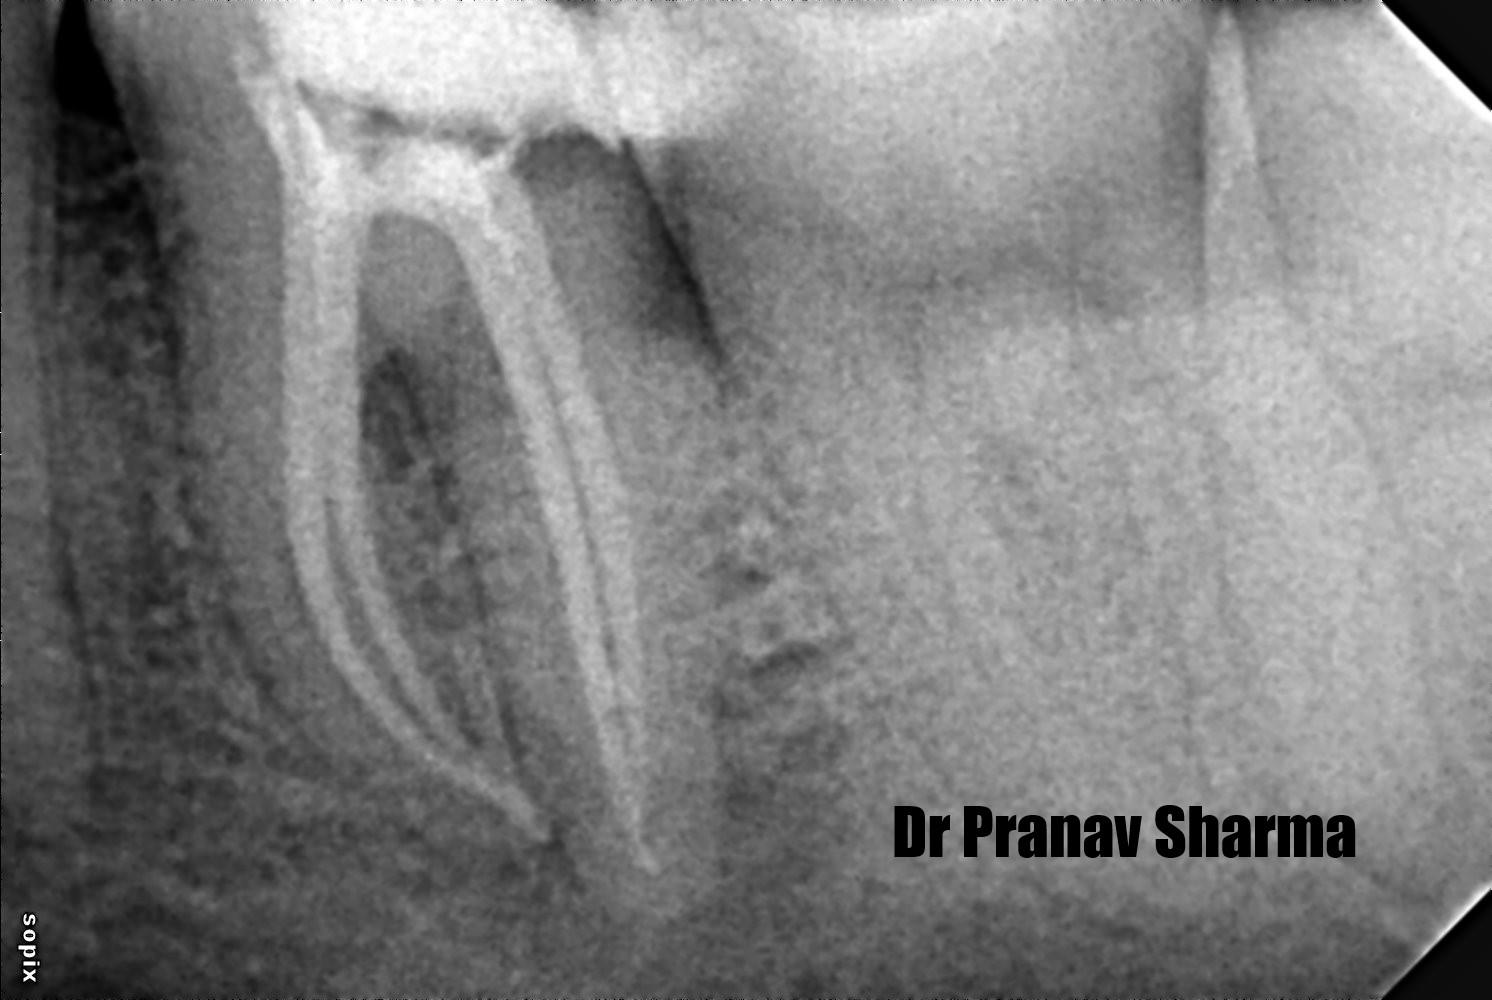

Xray